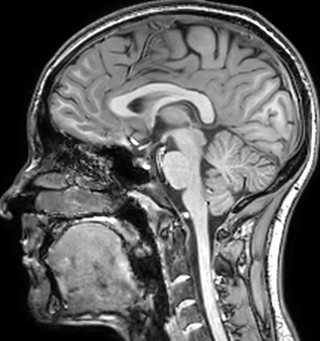

The techniques for measuring myelin have changed a lot over the years. “Since we are using the Elition, our myelin water images are much better. We're now acquiring 1 x 2 x 5 mm voxels and displaying at 1 x 1 x 2.5 mm. For a whole brain we can now measure the fraction of water in the myelin component in only about five or six minutes,” Dr. MacKay says.

of limiting MWI to the brain, even without the cerebellum, we can now spend about the same amount of time and scan the whole brain and the cervical spinal cord, which is a huge boost for us.” Dr. Rauscher says, “For MWI we perform 3D T2 with 32 or more echoes. This used to take a long time, but with Compressed SENSE we can decrease this to ten minutes for the whole head. Because of the large field of view (FOV) on the readout direction, we even get information from the brainstem, which we previously missed when we were using the GRASE approach. Having the whole head scan is nice because it has spatial resolution, orientation and FOV that are comparable to the standard 3D clinical MS scans, including the FLAIR and 3D T2, and a 3D T1 for brain volume.”

According to Dr. MacKay, MWI images benefit from Elition’s high quality gradients. “We need good gradients because we want to be able to do multi-echo sequences that have short TE times.”

Dr. Rauscher says, “With better gradients we can use a shorter echo spacing on the spin echo, so we get better sampling of the rapidly decaying myelin signal, which typically has T2 of around 10-20 milliseconds at 3 Tesla. If we can reduce echo spacing from about 8 to 5-6 milliseconds, we get a much better sampling of the short decay component and increase our SNR, which is a big advantage. The same is true for multi-echo gradient echo which we use for susceptibility mapping and for mapping venous vessels in MS.”